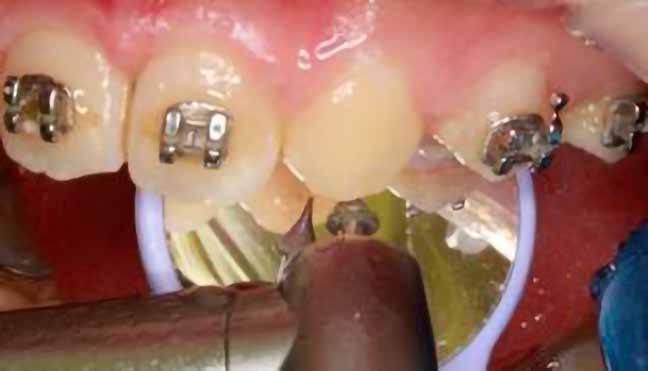

A kezelés első lépéseként az összes maradó fogra breketteket rögzítettünk. A felső fogív nivellálása, a ferde tengelyállá-

Dr. Kazem Dalaie, dr. Samin Ghaffari, dr. Mazir Mir (Irán, Németország) 1. a ábra: Az intraorális felvételen jól látható a jobb felső nagymetszőfog lehetséges impakciójára utaló foghiány.

sok korrigálása, valamint az impaktálódott fog előtöréséhez szükséges hely megteremtését követően, egy merev acél ív segítségével stabilizáltuk a fogakat. Ezt követően elvégeztük a jobb felső nagymetszőfog sebészi feltárását. A fog koronáját csupán lágyrész borította, ezért nem volt szükség a csontállomány elvételére. A felszabadítás során egy 975

nm-es hullámhosszon pulzáló üzemmódban alkalmazott lézert használtunk (LaserHF standard, Hager & Werken). A teljesítménye 3 W, az aktív ciklus-idő 50%-os, a vezetőszál átmérője pedig 0,4 mm volt (2. ábra). A lézert 150 másodpercen keresztül alkalmaztuk. A fogat borító lágyrészek eltávolítását követően egy láncos brekettet rögzítettünk a metszőfog bukkális felszínére. A műtétet követően nem tapasztaltunk vérzést, nem alakult ki oedema, valamint a páciens sem számolt be fájdalom vagy bármely egyéb kellemetlenség fennállásáról. A felszabadítást követően a páciens minden hónapban háromszor jelent meg a felszabadított területre ránövő lágyrészek és az íny lézeres eltávolítása céljából. A beavatkozások során ugyanazt a lézer készüléket használtuk, mint amivel a felszabadítást végeztük. Közvetlenül a felszabadítást követően megkezdtük a fog finom extrudálását a láncos breketthez kötött füzérgumi segítségével.

2. ábra: Az impaktált fog lézerrel asszisztált sebészi feltárása. 3. ábra: A kezelés megkezdését követő 15. hónapban megfigyelhető a sikeres felszabadítást, fogmozgatást és pozicionálást követően látható állapot.